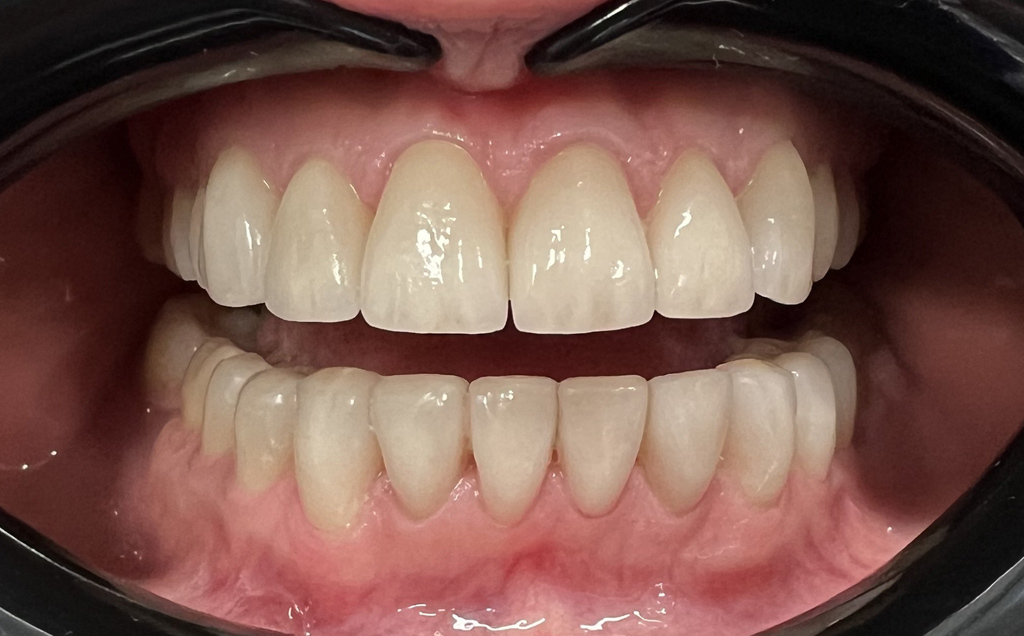

Zaprezentujemy serię poruszających historii pacjentów, którzy zdecydowali się na kompleksowe leczenie dentystyczne. Od przypadków zaawansowanej próchnicy, przez wypadki, które wymagały rekonstrukcji zębów, po pacjentów marzących o hollywoodzkim uśmiechu dzięki zastosowaniu licówek – każda historia jest dowodem na to, jak nowoczesna stomatologia może odmienić życie.

Skupimy się na innowacyjnych technologiach i metodach leczenia stosowanych w naszej klinice, które sprawiają, że te metamorfozy są możliwe. Od cyfrowego projektowania uśmiechu (DSD), przez ortodoncję i implanty, po zaawansowaną chirurgię szczękowo-twarzową. Omówimy, jak te techniki pracują razem, aby osiągnąć najlepsze wyniki.